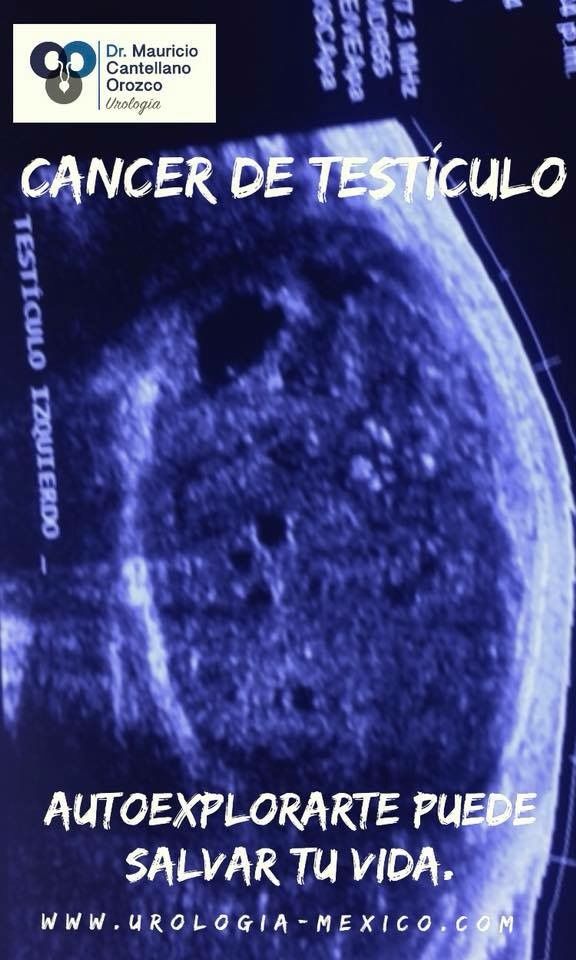

Cáncer en la vía urinaria: Riñón, Uréter, Vejiga, Próstata